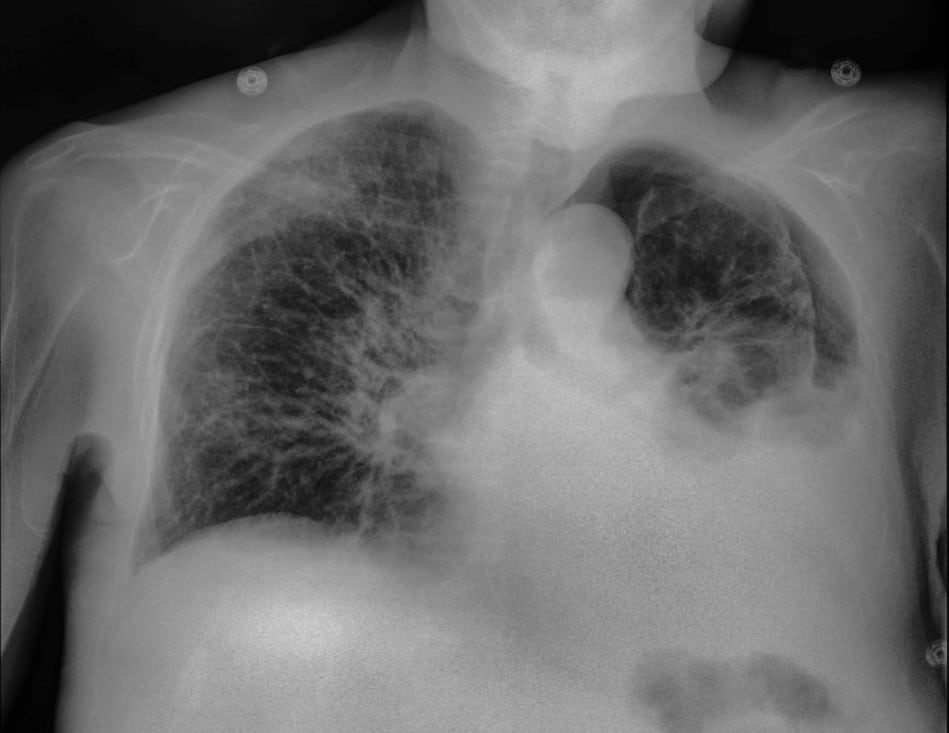

Conventional radiography compresses all anatomical information into a single image. In complex clinical environments, overlapping structures may obscure clinically relevant findings.

Spectral X-ray imaging separates bone and soft-tissue information from a single exposure, producing multiple image outputs while maintaining the same workflow as standard radiography.

Reveal™ 35C detectors use SpectralDR® technology to acquire multiple spectral images from a single X-ray exposure.

Each exposure produces:

- a conventional digital radiography image

- a bone image

- a soft-tissue image

These images allow clinicians to separate overlapping anatomical structures and visualize areas that may be less visible in conventional radiographs.

Unlike traditional dual-energy imaging techniques that require multiple exposures, SpectralDR captures these images simultaneously with a single exposure, eliminating motion artifacts and maintaining the same clinical workflow as standard portable radiography.

Soft-tissue images can reduce rib overlap and may improve visualization of pneumothorax during bedside chest X-ray examinations.

Spectral imaging can enhance visualization of lung opacities by separating bone from soft tissue, potentially improving evaluation of pneumonia and other lung conditions.